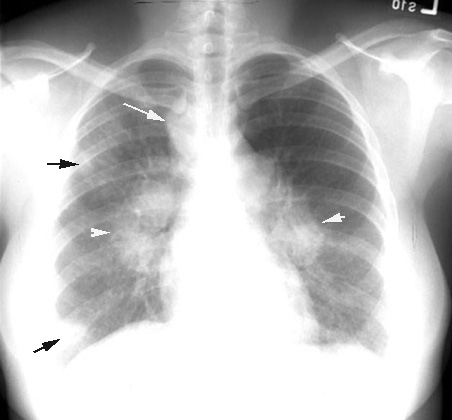

Sarcoidosis

Potato nodes

Arrowheads: Symmetrical hilar nodes

White arrow: Enlarged paratracheal nodes

Black arrows: Alveolar lung infiltrates